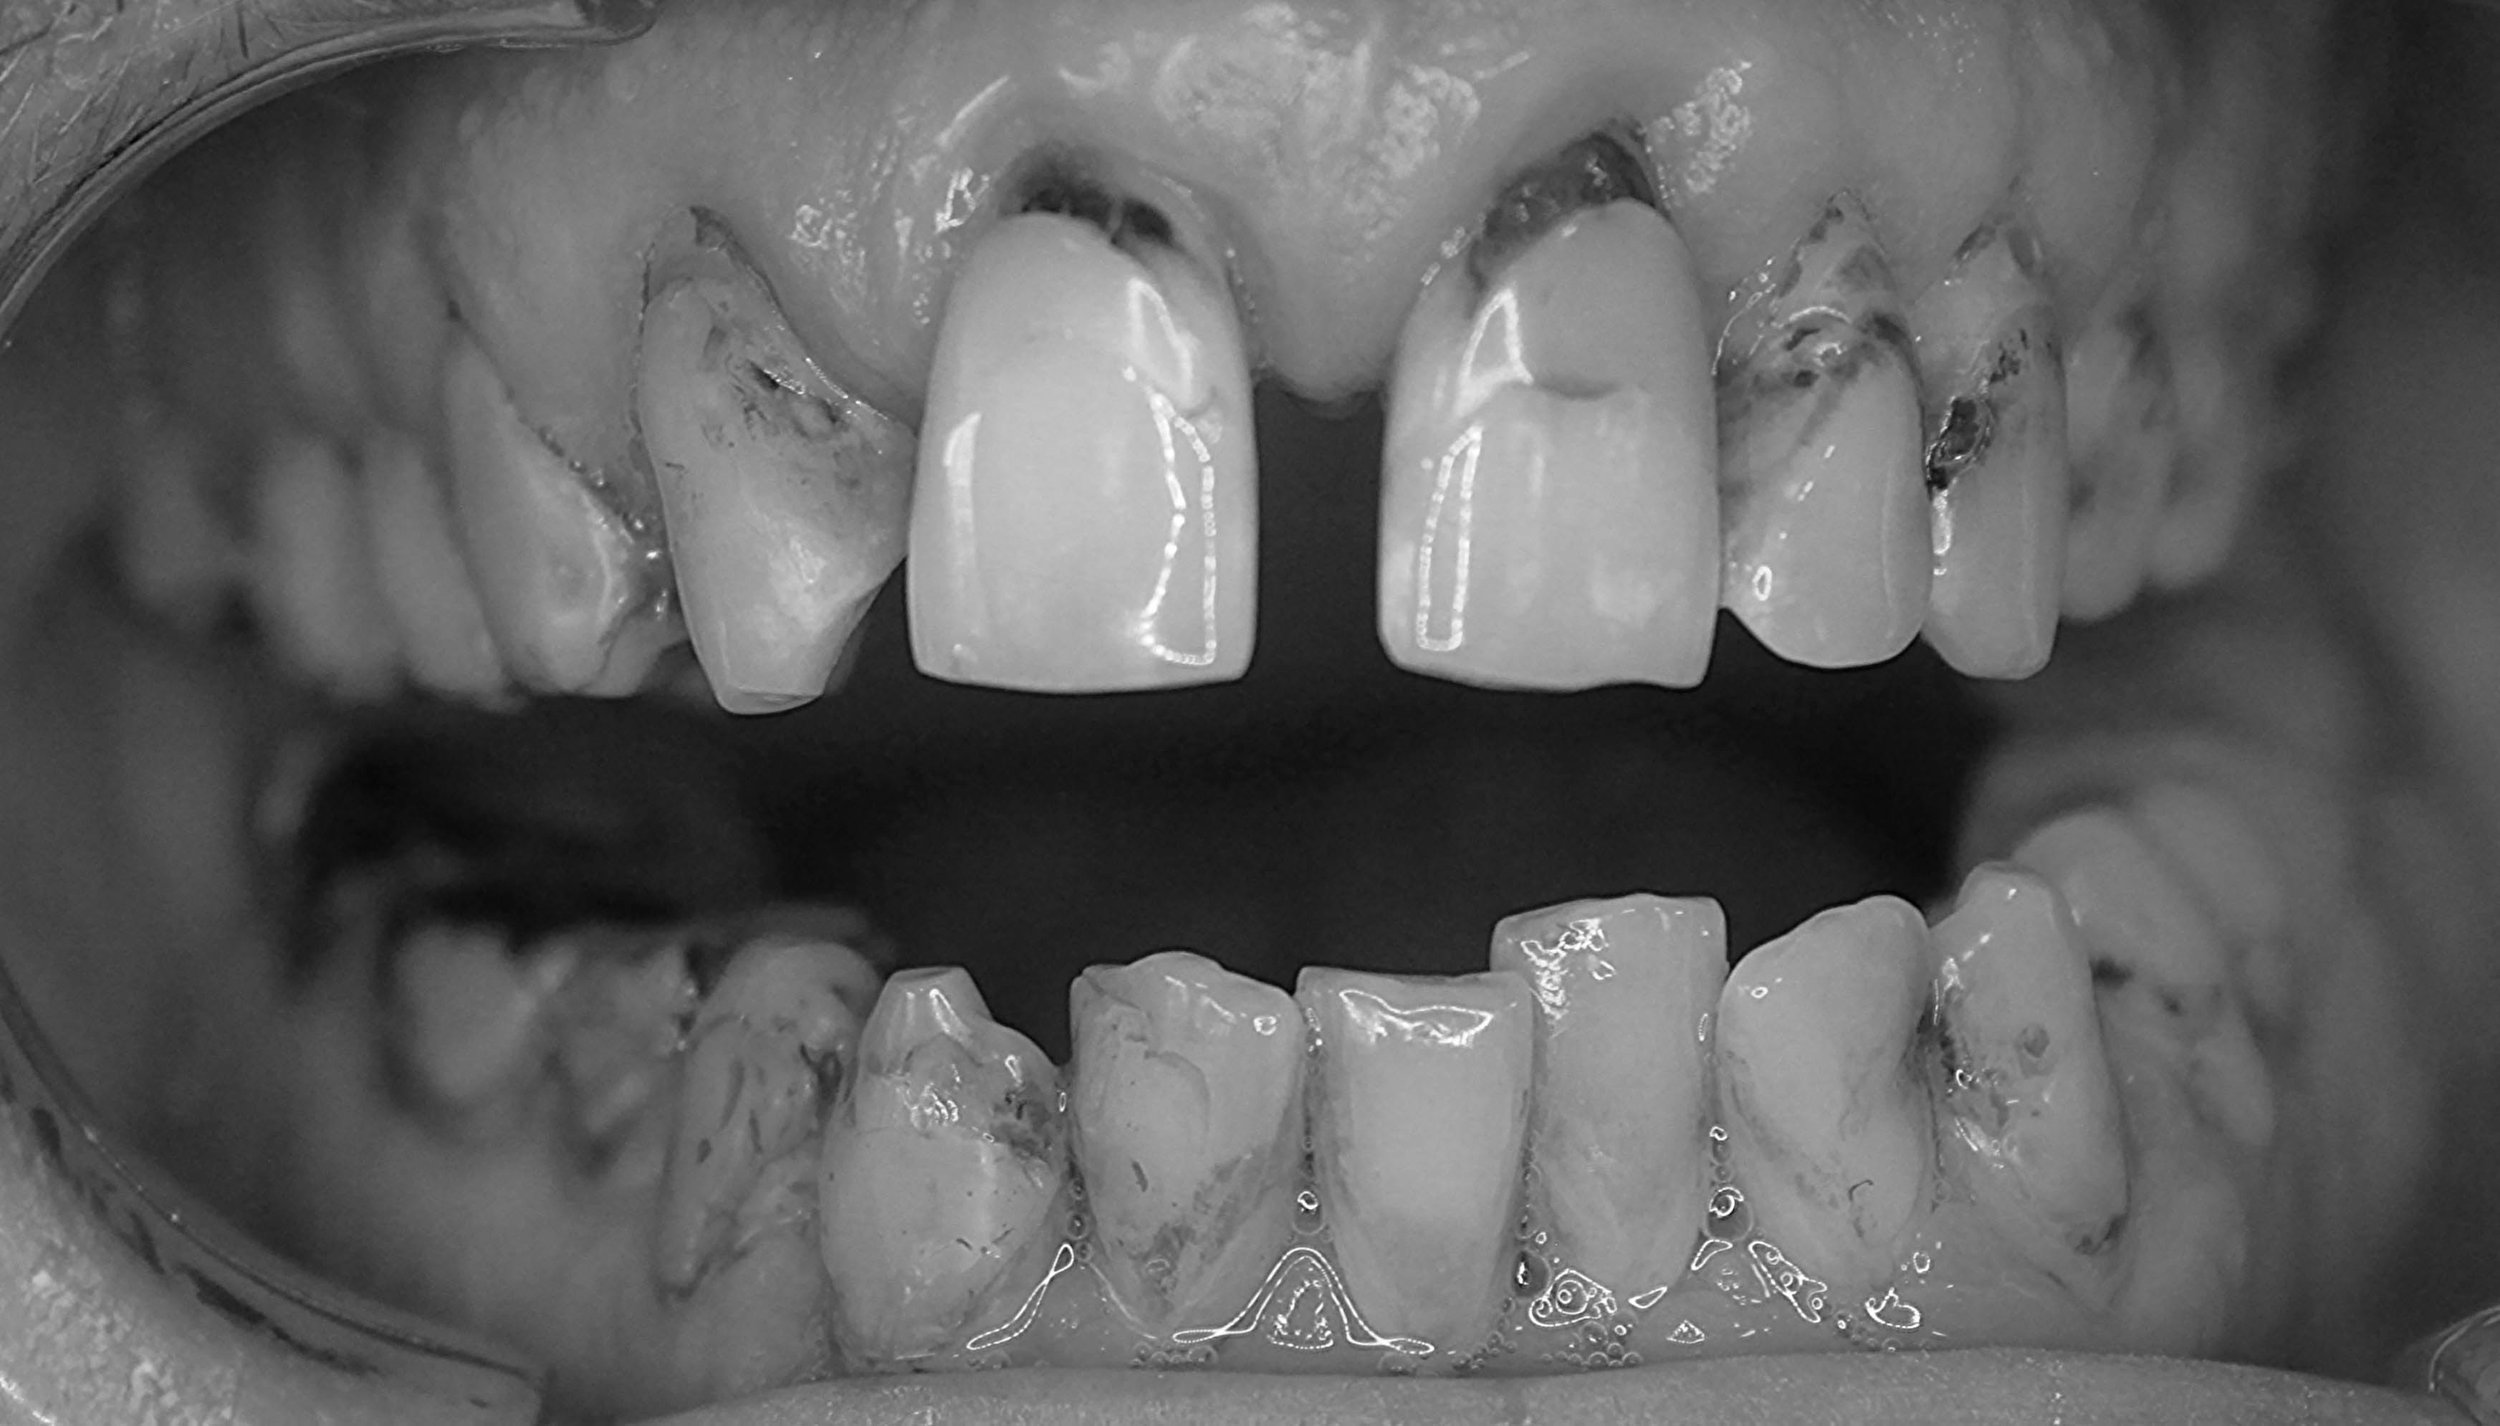

AVANT / APRÈS